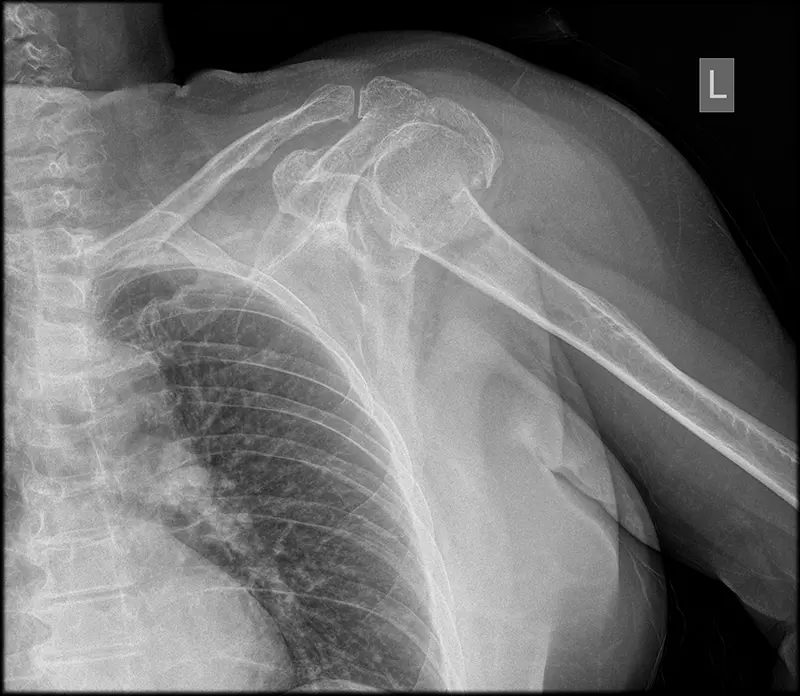

Proteza urazowa

W przypadku złamania kości ramiennej istnieje kilka różnych podejść do leczenia, w tym zarówno podejścia zachowawcze, jak i chirurgiczne. Dla pacjentów w podeszłym wieku lub tych z ryzykiem martwicy głowy kości ramiennej, proteza barku może być rozważana jako opcja leczenia.

Proteza barku, czyli zastąpienie głowy kości ramiennej fragmentem metalowej kuli, jest jednym z rozwiązań w przypadku złamań kości ramiennej. Jest to szczególnie istotne w przypadku pacjentów w starszym wieku lub w sytuacjach, gdy istnieje ryzyko martwicy głowy kości ramiennej.

- Proteza połowiczna i odwrócona proteza: W przypadku złamań kości ramiennej, częściej stosuje się protezę połowiczną lub odwrócone protezy. Odwrócona proteza była popularna w przypadku złożonych złamań kości ramiennej (złamania 4 fragmentowe głowy kości ramiennej), szczególnie u starszych pacjentów. Natomiast proteza połowiczna, czyli proteza zastępująca jedynie głowę kości ramiennej, może być stosowana w bardziej standardowych przypadkach złamań. Głównie u osób młodych, gdzie ryzyko martwicy głowy kości ramiennej po złamaniu jest wysokie np. przy złamaniach szyjki anatomicznej głowy kości ramiennej.